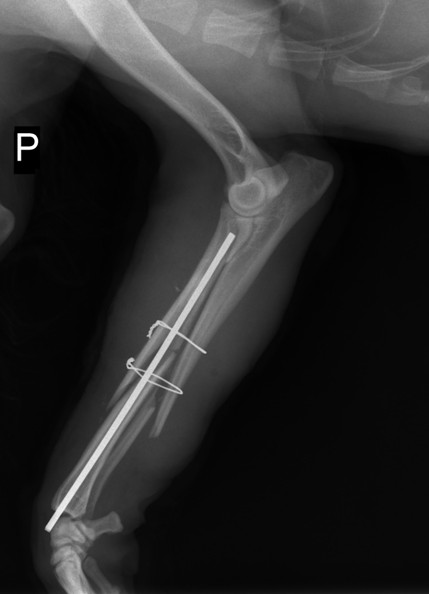

Mirella hat uns die Röntgenaufnahmen von Jimi, vor und nach der OP, als Datei geschickt.

Sie schreibt : Die Aerzte haben gesagt, dass der Bruch kompliziert war. Ein Splitterbruch

ohne OP verheilt nicht. .Jimi hat die OP sehr gut verkraftet. Er ist stark , brav und laechelt.

Er bleibt bis morgen in der Klinik , dann bringe ich ihn zurueck ins TH. In zwei Wochen hat

Jimi einen Termin in der Klinik (Entfernung Naht und Verband). Bis dahin wird Jimi die Schmerzmittel bekommen. Laut Aussage der Tieraerzte ist Jimi transportfaehig (auch mit dem Verband). Der allgemeine Gesundheitszustand von ihm ist gut. Das einzige, was Jimi jetzt nicht darf, ist das Laufen. Der Transport wird dem Hund nicht schaden.